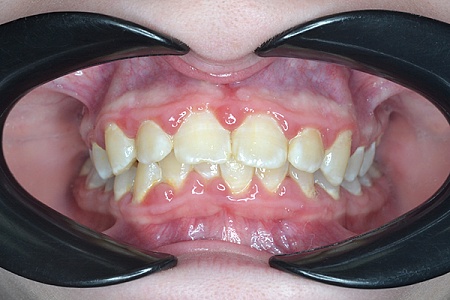

Работы наших врачей